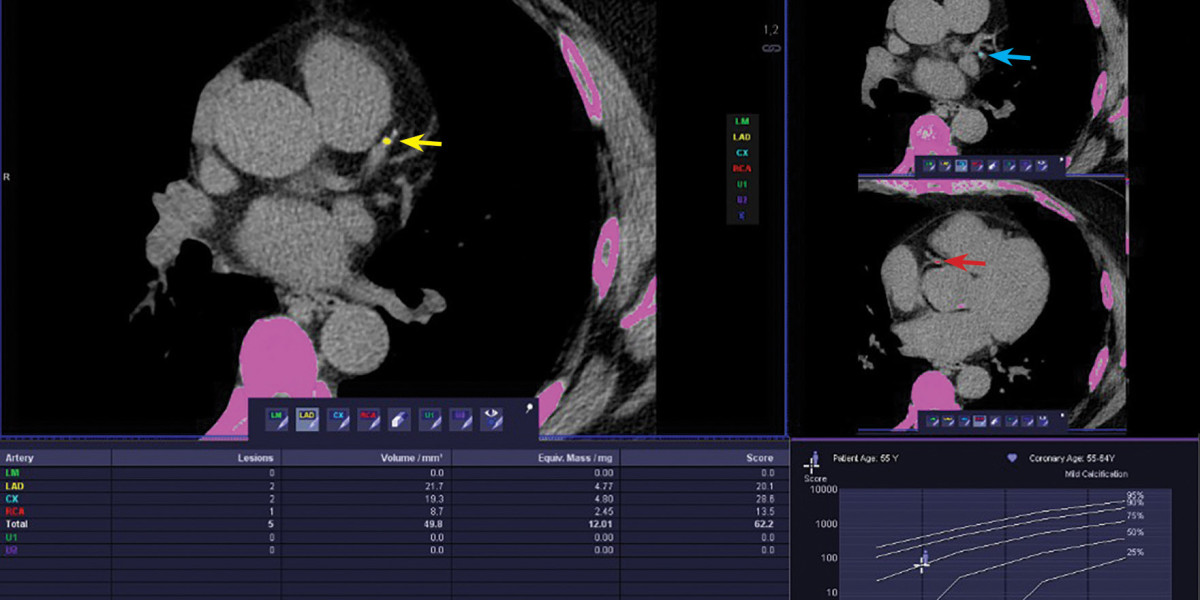

CT Scan Procedure Explained: What Happens During the Exam | #body scan

CT Scan Procedure Explained: What Happens During the Exam

CT scan is an imaging process that does not involve any kind of insertion. This scan includes the use of X-rays or MRI to capture detailed and comprehensive images of the lungs from all angles. The detailed pictures of the lungs highlight the abnormalities such as tumors within the lungs o